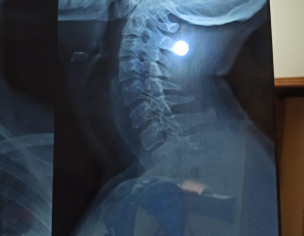

I have been stiff neck problems for quite sometime now where I wake up with a stiff neck which leads to headaches. I work in IT and have a desk job 9 hours a day. I have recently had my neck X-ray done on the advice of my doctor. I seek help as I will not be able to visit my doctor due to work. Doc works in the weekdays and so do I. I need someone qualified to take a look at my x-ray and tell me if there is anything wrong. I would be grateful. Bless you!

Attach Photo here: